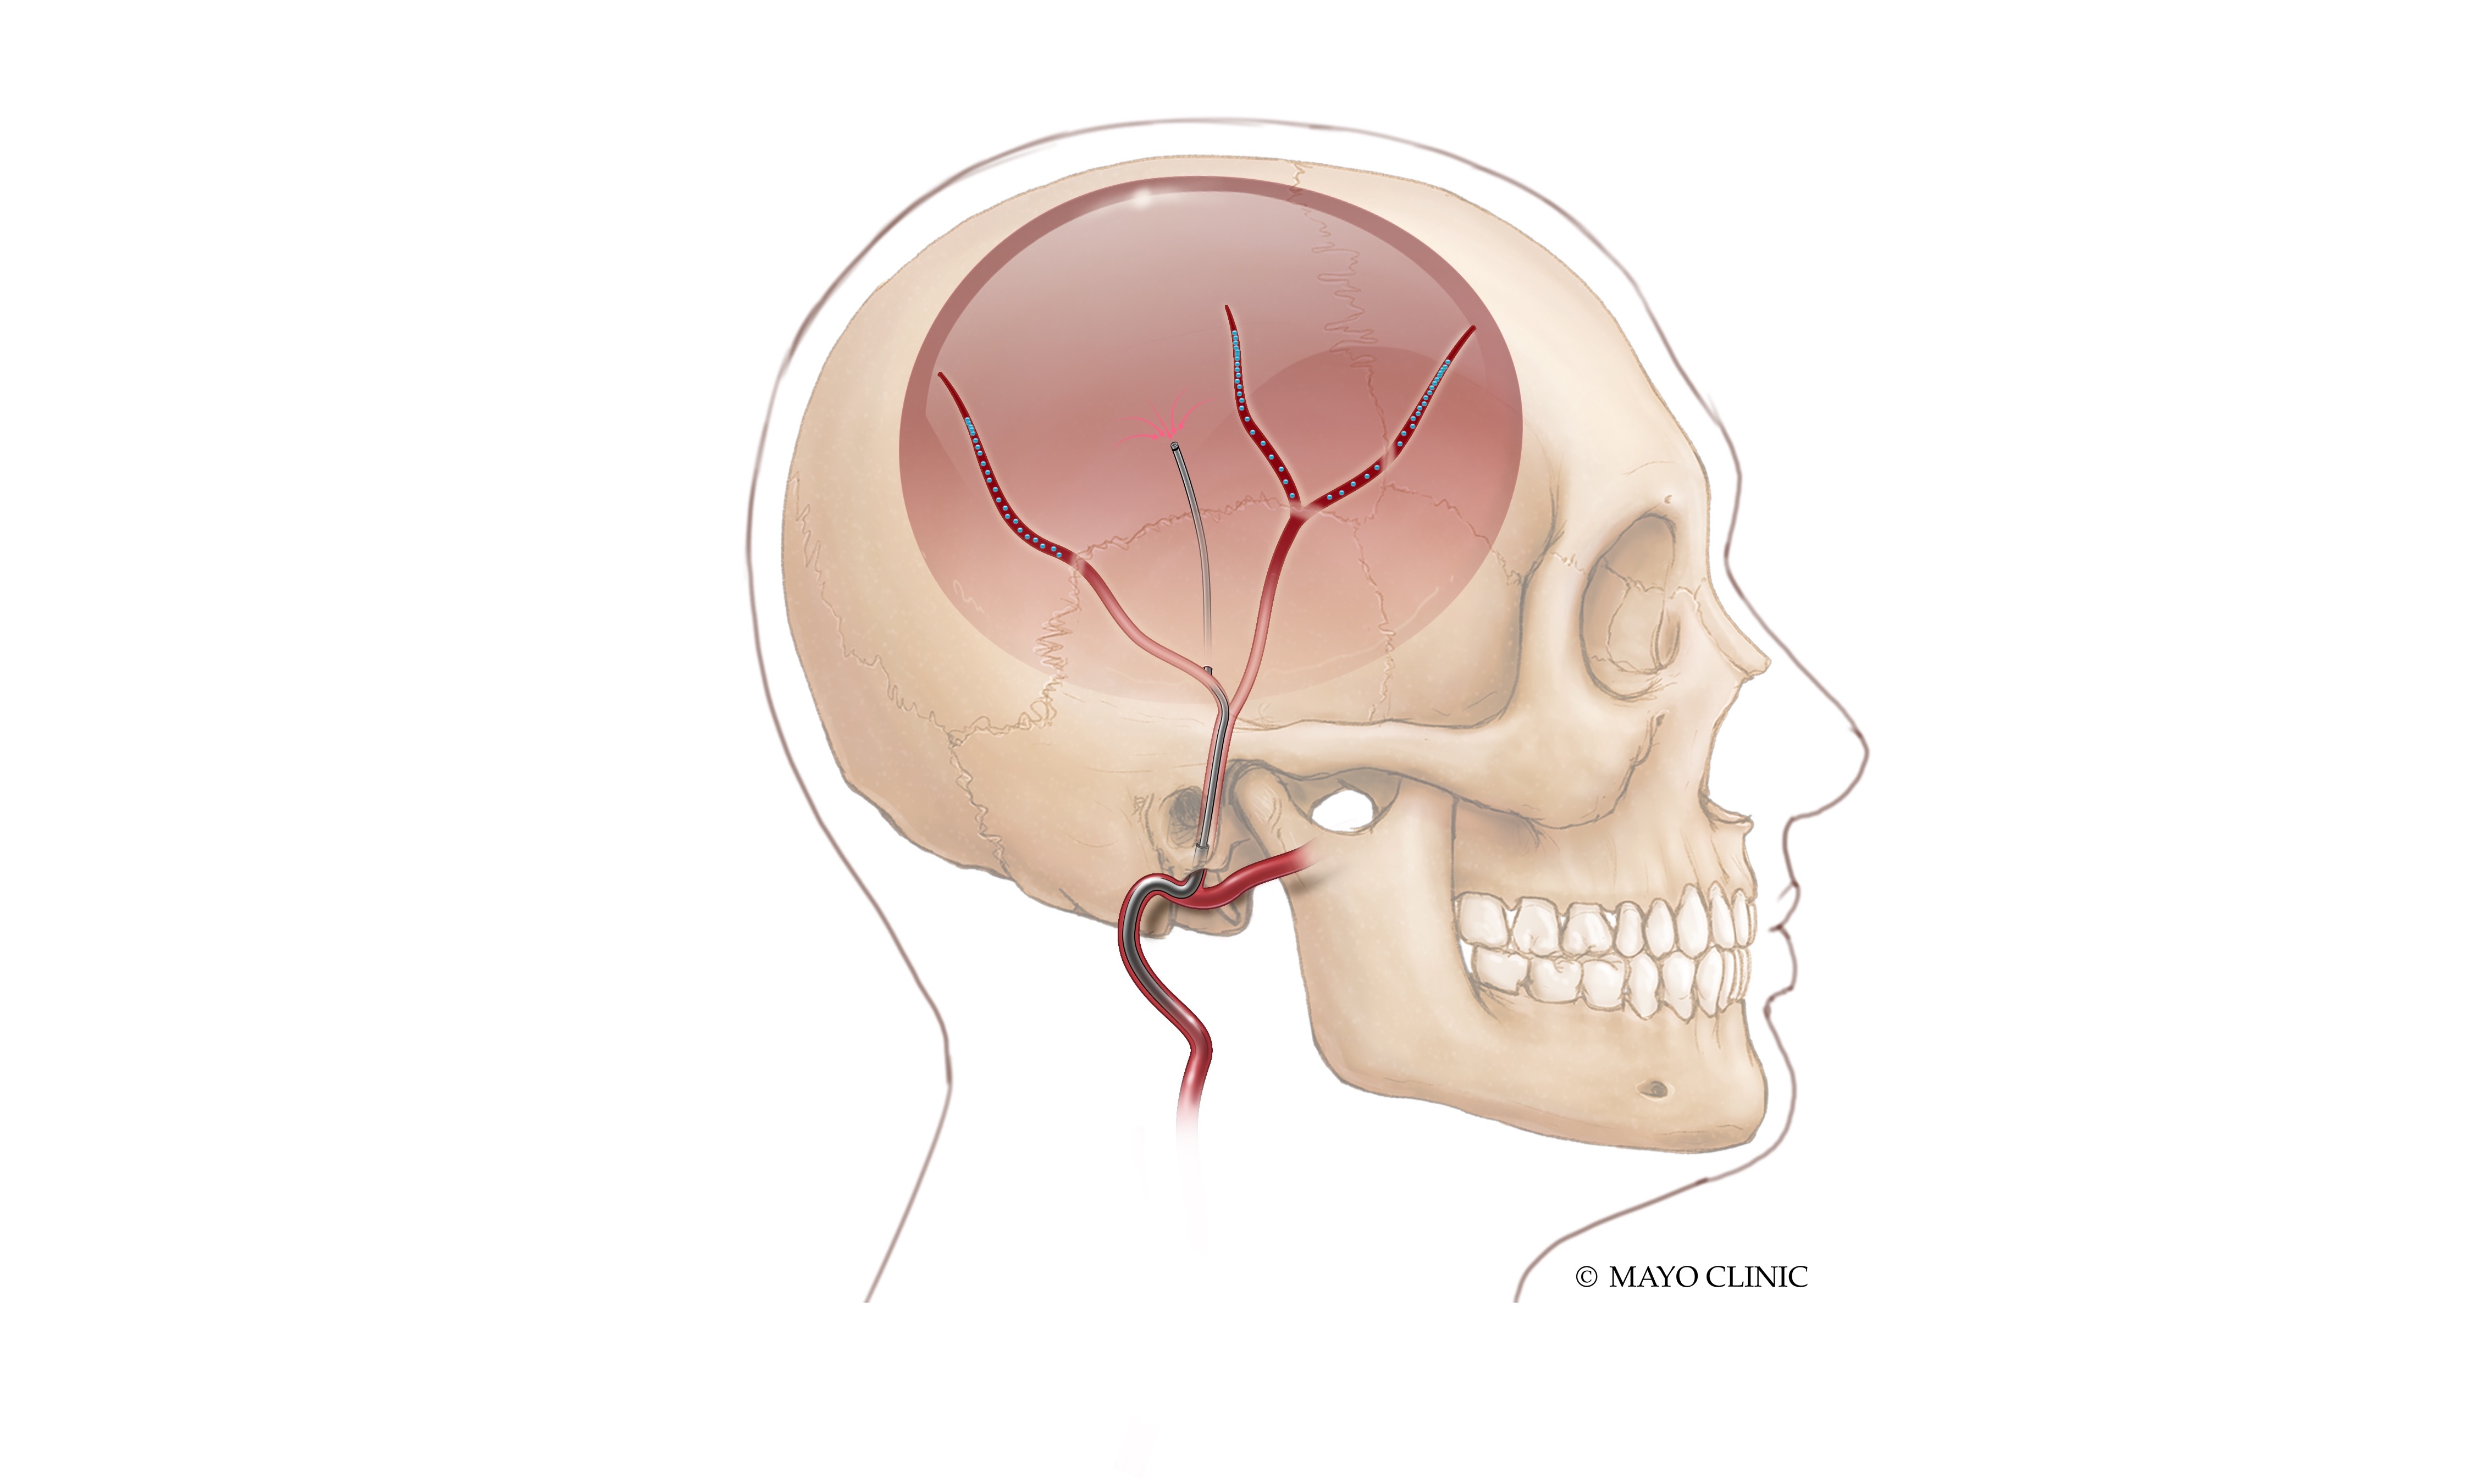

Abstract Body: Introduction: surgical evacuation of non-acute subdural hematoma (SDH) for rapid brain decompression and middle meningeal artery embolization (MMAe) to prevent re-bleeding as a surgical adjunct is becoming a dominant treatment paradigm of symptomatic SDH. However, this approach requires two different interventions with their associated risks, prolonged ICU/hospital stay and increased costs. An endovascular technology was developed for transvascular access to the intradural space, drainage of SDH and MMAe. We report the procedural results and 6-month follow up of the first three consecutive patients treated with this technology. Methods: a prospective, single-arm, first-in-human study (EMBODRAIN Study) was conducted to evaluate the safety and feasibility of endovascular drainage of non-acute SDH and MMAe using a purpose-built endovascular technology (Endovascular Horizons, Inc). Results: three consecutive patients (males, 76 years ±5) were treated and completed the pre-specified 6 months follow-up. Acute clinical success (defined as MMAe and transvascular drainage of the SDH with no conversion to open surgical drainage) and acute technical success (defined as ability to create a leak-proof transvascular passageway and access the intradural space, drain the SDH and occlude the MMA) was achieved in all cases (3/3). No Serious Adverse Events (SAE) were recorded at 30-days. The SDH volume at baseline (before intervention) was on average 296 ml, and decreased immediately post-procedurally to 25ml, corresponding to a 92% volumetric reduction on average. The SDH thickness at baseline was on average 25 mm, and decreased post-procedurally to 11 mm. The midline shift at baseline was on average 8 mm, and decreased post-procedurally to 3 mm. At 6-months the head CTs showed an average SDH volume of 8ml, SDH thickness of 3mm, and midline shift of 0mm. The pre-morbid Modified Rankin Scale Score was 0.33 on average, was 3.66 at presentation with the SDH, and decreased to an average of 2.33 at 72hrs post-intervention. At 6 weeks, 3 months and 6 months follow-up, all patients were found to have a mRS of 0. During the study duration there were no SDH recurrence or progression requiring surgery, hospital readmission and deterioration in neurological function. Conclusions: this report presents the first cohort of patients with symptomatic non-acute subdural hematomas to successfully undergo endovascular drainage of SDH and MMAe in a single, fully endovascular procedure.